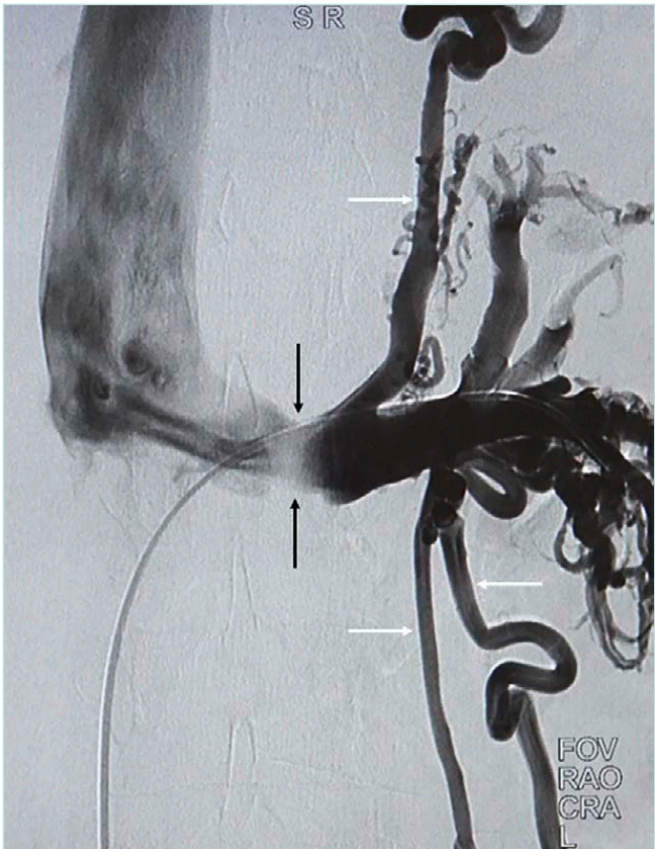

Venography is best reserved for preoperative planning. It demonstrates LRV narrowing, collaterals, and venous reflux (Figure 2). Pressure readings further aid diagnosis.27 However, some normal individuals may exhibit >3 mm Hg gradients, and patients with collaterals may show normal pressures.

Figure 2. Venography demonstrates maximal compression and poor opacification of the aortomesenteric level of LRV (black arrows) with preferential collateral flow via the

splenic venous plexus and gonadal veins (white arrows). LRV, left renal vein.